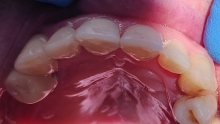

Clinica LUY ESTHETIC ART dispune de ultimele tehnologii in domeniul stomatologic si ofera solutia tratamentelor endodontice, pentru a incerca sa salveze un dinte care a fost distrus in proportii mari. Specialistii nostrii efectueaza acest tratament in mod corespunzator, pentru a evita aparitia altor complicatii ce implica interventii mai complexe: rezectia apicala sau riscul de a pierde dintele.

Stresul, fumatul, o igiena dentara precara, dar si modul de alimentatie duc la formarea cariilor. Acestea, netratate, favorizeaza aparitia infectiilor care vor dezvolta chisturi. Astfel de probleme se trateaza cu ajutorul tratamentului endodontic, zona respectiva fiind bine izolata pentru a preveni alte infectii. Atunci cand masurile nu sunt luate din timp, pulpa infectata moare si se formeaza chisturi la nivelul radacinii, iar interventia va deveni mai complexa.

Tratamentul endodontic este mult mai eficient si usor atunci cand bacteriile nu ajung pana in varful radacinii si nu apar chisturile.

La Clinica LUY ESTHETIC ART tratamentul endodontic poate fi efectuat pe durata mai multor sedinte, doar cand chisturile dezvoltate sunt medii. Tratamentul nu este dureros deoarece se realizeaza sub anestezie. Pe langa talent, cunostinte medicale, dar si meticulozitate, acest tratament, presupune folosirea unei aparaturi performante: